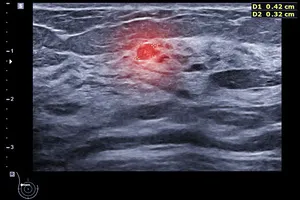

초음파 검사 결과를 바탕으로 담당 의사로부터 자세한 설명을 듣습니다. 혹의 모양, 크기, 경계, 내부 에코 등 초음파 소견을 종합적으로 판단하여 추가적인 검사가 필요한지 여부를 결정합니다.

- 불규칙한 모양, 경계가 불분명함, 주변 조직 침윤 등의 특징, 조직 검사를 통해 최종적으로 확진됩니다.